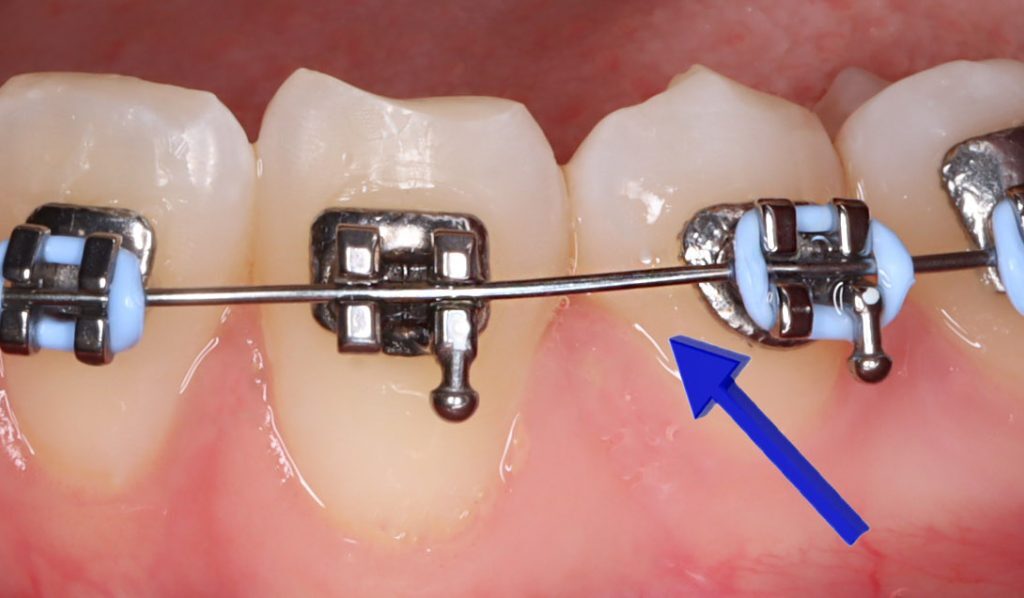

Aparelho Ortodôntico Fixo: Com brackets colados aos dentes e fios metálicos ajustáveis, é uma opção tradicional e eficaz para correções mais complexas.

4. Manutenção e Ajustes Periódicos

Para garantir o sucesso do tratamento, são necessárias consultas regulares para ajustes.

Nessas visitas, o ortodontista verifica o progresso e realiza alterações nos arcos ou nos alinhadores para manter os dentes em movimento na direção planejada.